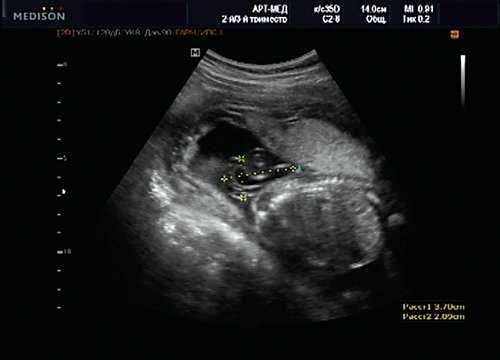

При эхокардиографии изучались четырехкамерный срез сердца плода (рис. 1) и срез через три сосуда (рис. 2). УЗИ проводилось трансабдоминальным датчиком, лишь при необходимости (затрудненная визуализация) использовался внутриполостной датчик. Четырехкамерный срез сердца плода при ультразвуковом сканировании трансабдоминальным датчиком визуализировался в 85% случаев, срез через сосуды - в 73%, при использовании трансвагинального датчика эти цифры существенно возрастали до 100 и 91% соответственно. Оптимизация пренатальной диагностики ВПС может быть достигнута путем строгого соблюдения основных методических правил. При оценке четырехкамерного среза плода необходимо оценить нормальное расположение сердца плода, исключив его эктопию (рис. 3), положение оси сердца плода, что не представляет никаких трудностей, нормальные пропорции и размеры камер сердца, движение створок атриовентрикулярных клапанов должно быть свободным, септальная створка трикуспидального клапана должна располагаться ближе к верхушке сердца (рис. 4). При оценке среза через три сосуда необходимо оценить взаиморасположение сосудов и их диаметр.

Рис. 1. Беременность 12 недель. Четырехкамерный срез сердца плода. Отчетливо видны камеры сердца.